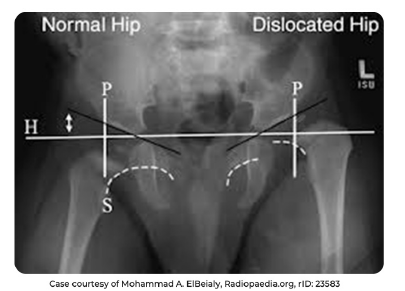

Traçar uma linha entre as cartilagens trirradiadas (Hilgenreimer)

A partir dela, traçar uma linha que margeie os dois cantos do acetábulo

• indice acetabular

. N = <30°